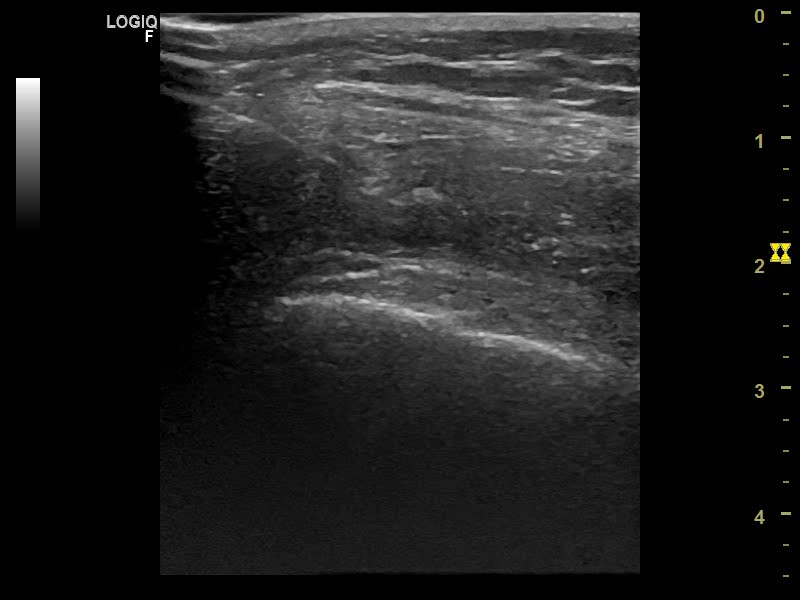

Tras anestesia con mepivacaina y realizar adecuada asepsia de la zona y con campo esteril se procede al drenaje mediante artrocentesis dirigida por ecografía con aguja 21 G (intramuscular) extrayéndose 30 cc de líquido sanguinolento. (imagen 3) Sin retirar la aguja se procede a infiltrar betametasona (Celestone Cronodose) (imagen 4).

Descripción de los hallazgos ecográficos y las imágenes más relevantes para la resolución del caso